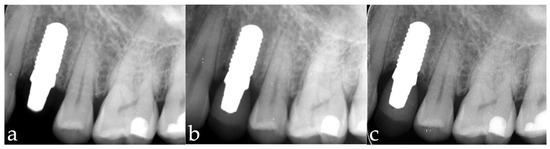

3.1. Marginal Bone-Level Changes

3.2. Implant Survival